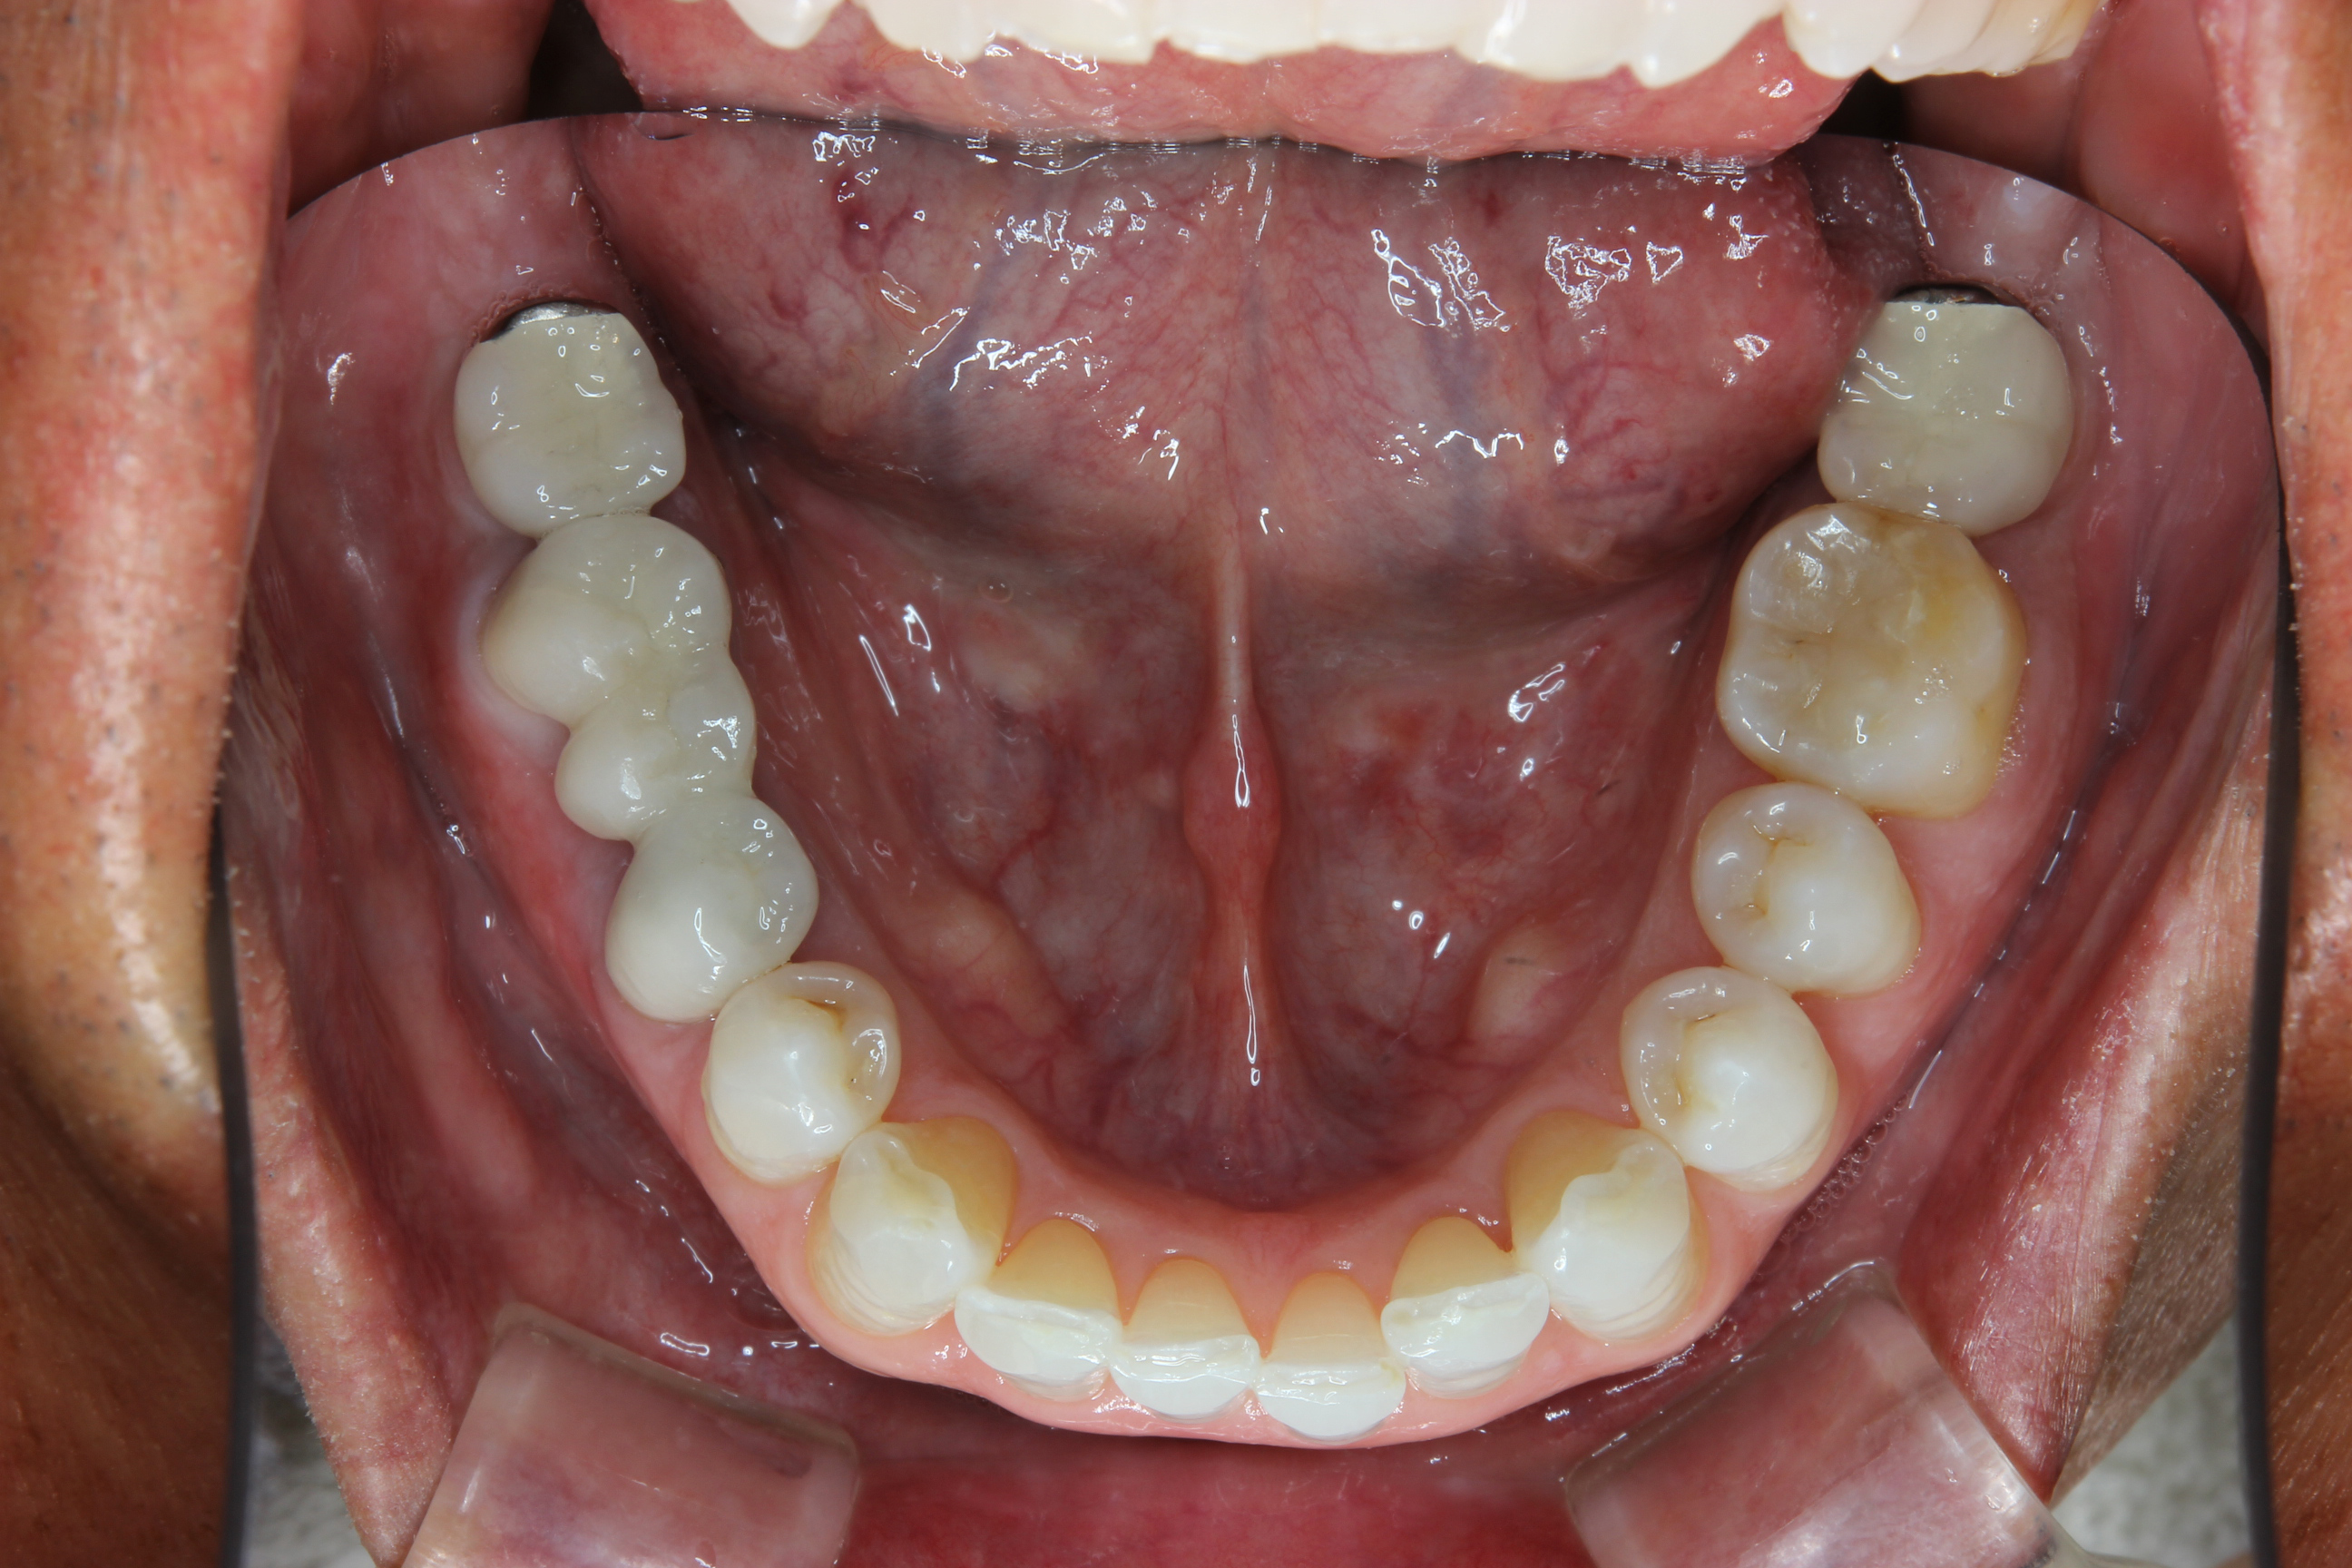

写真は、先に通院されていた奥様の紹介でお見えになった患者さん。

全体的にしっかりきれいに治したいとのことでした。

下顎左右の第2大臼歯(一番奥の歯)が欠損、それに伴い対合歯(噛んでいる歯)が挺出(飛び出す)しています。

また、右下のブリッジの不適合、正中(左右前歯の中央)のコンポジットレジンの形態不良などがありました。

下の写真は治療前。

下の写真が治療後です。

きれいになった口腔内を写真で見て、患者さんも喜んでくれました。